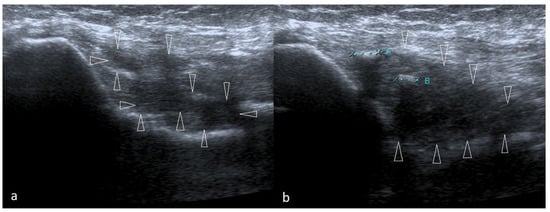

The Technique of Ultrasound Examination of the Medial Portion of the Elbow

4.8. Epitrochlear Lymphadenopathies